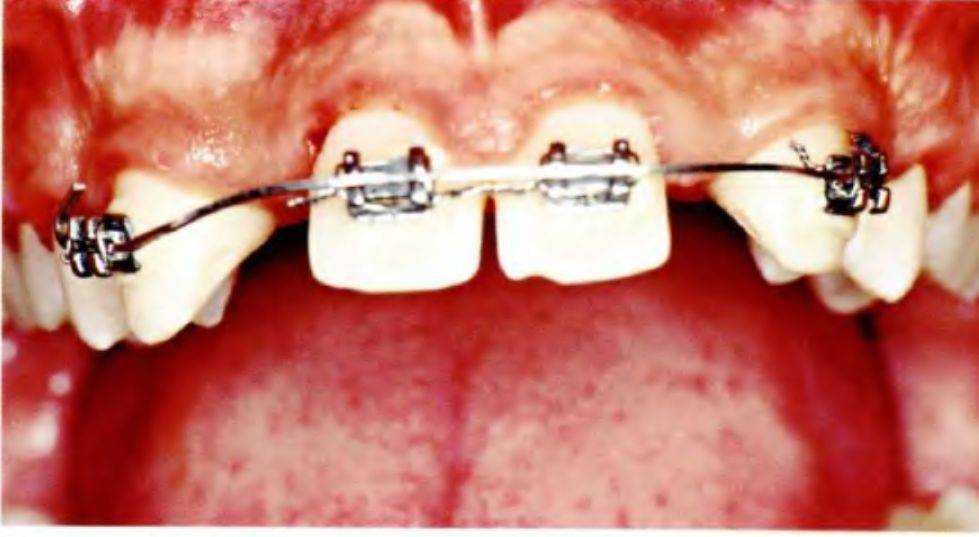

Рис. 5-3f. Вид после удаления проволоки

Из брекетов извлекли дугу (рис. 5-3f), на небных поверхностях клыков и центральных резцов отпрепарировали небольшие борозды (рис. 5-Зд). Перед получением полиэфирного оттиска брекеты закрыли воском (рис. 5-3h). Затем с помощью оттиска отлили рабочую гипсовую модель (рис. 5-3i и 5-3j). После этого ортодонтическую ретракционную дугу установили в прежнее положение для обеспечения ретенции (рис. 5-3 к).